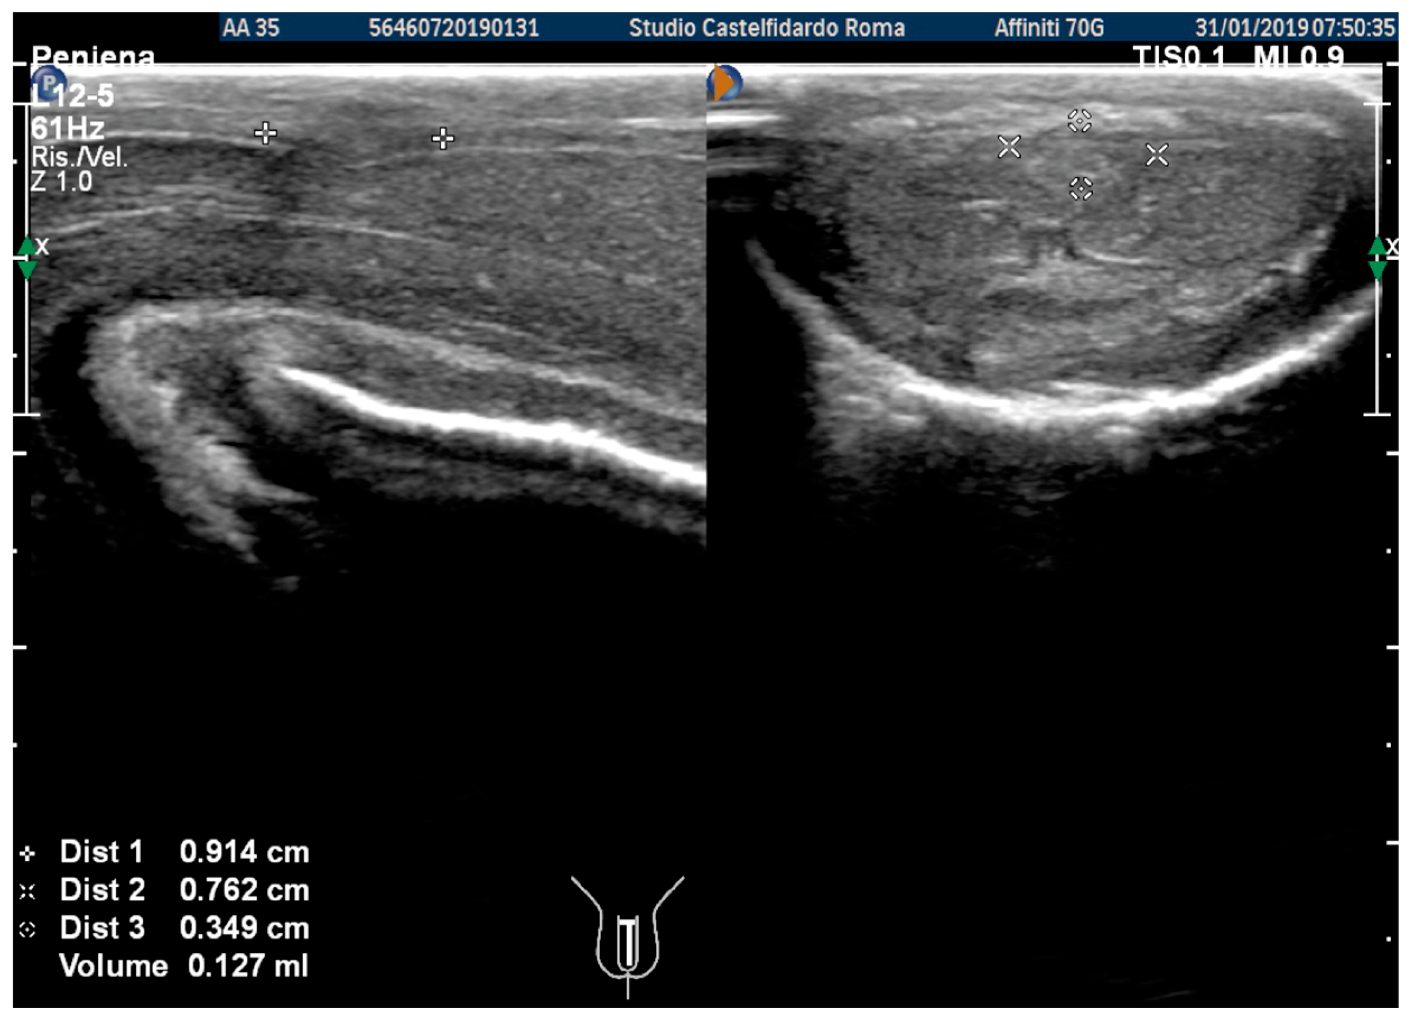

| 3 | 33 years | None | Middle third | (A) 20.6 × 15.2 × 4.42 mm volume = 724 mm3 + some small calcifications, the largest of which measured 1.9 × 4.1 mm | (A) 30-degree dorsal penile curvature | (A) score 2 | (A) score 26 | 3 years and 5 months | orally: Silymarin 400 mg + Ginkgo biloba 250 mg + Propolis 600 mg + Bilberry 160 mg + Vitamin E 800 IU/once a day, for 41 months. + topically: Propolis creme/twice a day/for 41 months. + peri-plaque penile injections: Pentoxifylline 100 mg (30 G needle) every 15 days for 6 months, and then monthly for 12 months, and then 1 injection every other month. for 12 months (total = 30 injections) |

| (B) No plaque detected | (B) None | (B) score 0 (after six months) | (B) score 27 |